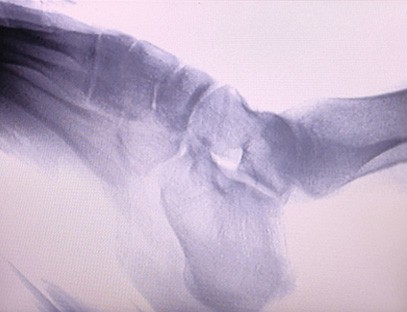

Mūsų ortopedinis rentgeno aparatas gali būti naudojamas įvairiose medicinos srityse, įskaitant ortopediją, neurologiją ir skubią mediciną. Jis dažnai naudojamas fluoroskopiniam žmogaus galūnių kaulų stebėjimui, veterinarijos ir naminių gyvūnėlių ligoninėms, sužeistųjų gydymui sporto aikštelėse, pastatuose, okeaniniuose laivuose, atokiose vietovėse ir karinių laukų vietose. Kai kurios klinikinės programos apima:

1. Lūžių, išnirimų ir kitų kaulų traumų diagnostika.

2. Sąnarių ligų, tokių kaip artritas, degeneracinė sąnarių liga ir osteoporozė, įvertinimas.